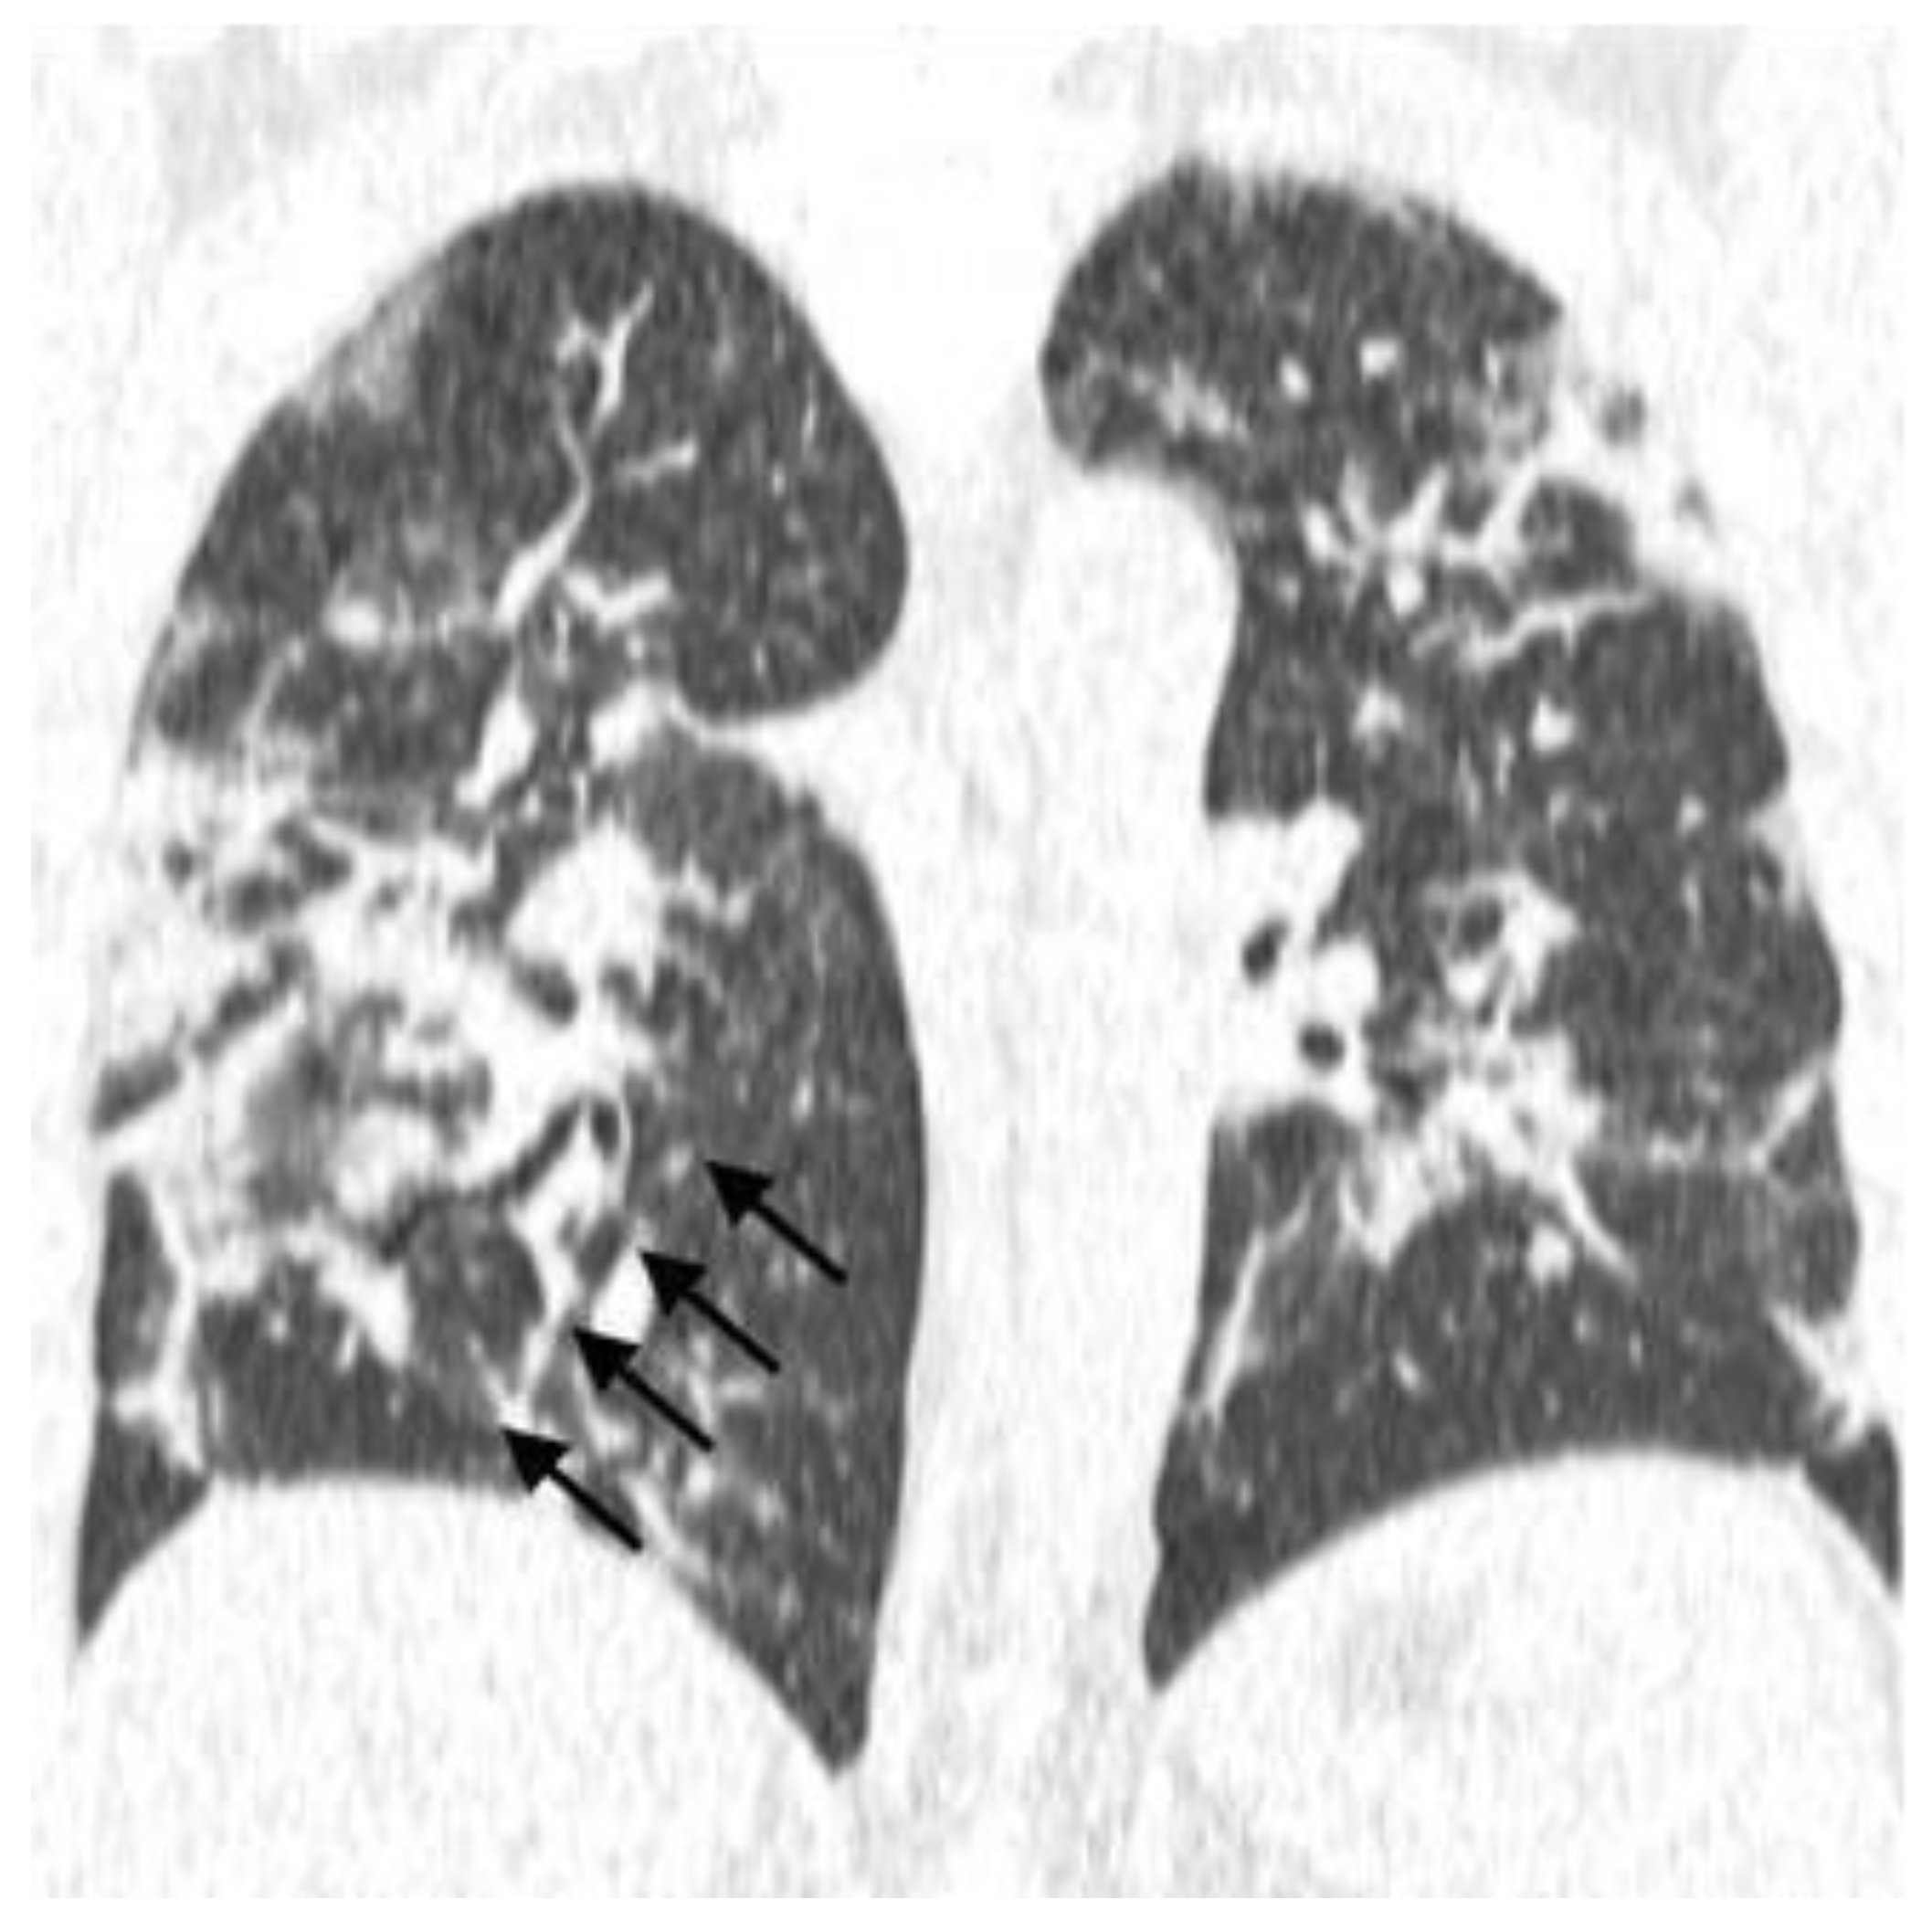

- Typical: Ground-glass opacities (peripheral, bilateral, rounded, and/or multifocal) or reversed halo sign; with or without consolidation; with or without mosaic paving;

| Ground-Glass Opacity | |||||||

| Yes | 47 | 63.5 | 9 | 60 | 38 | 64.4 | 0.75 |

| Mosaic Pattern | |||||||

| Yes | 19 | 25.7 | 3 | 20 | 16 | 27.1 | 0.42 |

| Consolidations | |||||||

| Yes | 22 | 29.7 | 4 | 26.7 | 18 | 30.5 | 0.52 |